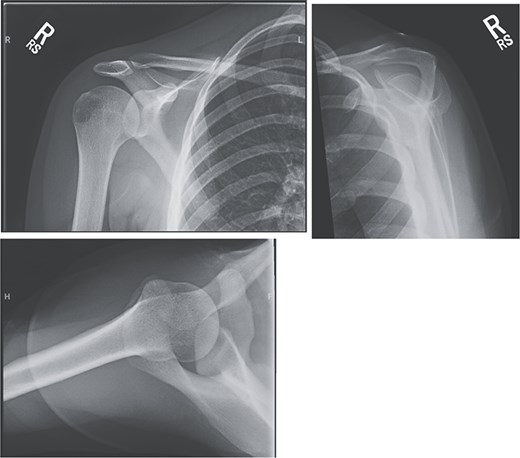

An 18-year-old, right-hand dominant woman presented reporting several weeks of right shoulder pain limiting participation in DIII collegiate volleyball. Examination revealed atrophy of the infraspinatus region. Muscle testing revealed weakness of infraspinatus and supraspinatus with reproducible symptoms. Radiographs were without transverse scapular ligament calcification (Fig. 1). Magnetic resonance imaging (MRI) arthrogram revealed low-grade undersurface fraying of the supraspinatus and infraspinatus tendons consistent with impingement, hypertrophic posterior inferior labrum, and no evidence of paralabral cyst (Fig. 2). Rest from hitting activities, anti-inflammatory medications, and periscapular strengthening therapy were initiated.

Radiographic imaging on initial presentation was without transverse scapular ligament calcification.